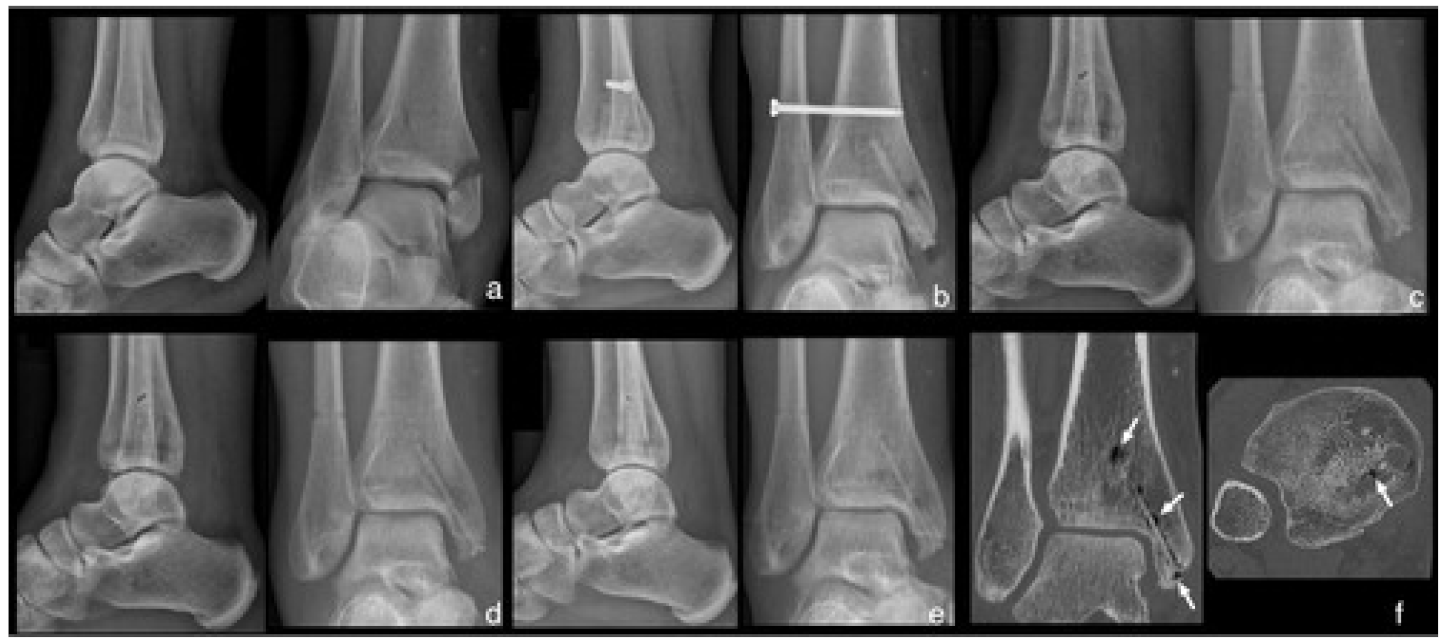

| Leonhardt H et al. [116] | Case series | Mandibular fracture | MgYREZr | 5 | Fracture healing, with restored function of the temporomandibular joint | One fracture of a screw |

| Leonhardt H et al. [111] | Retrospective observational study | Mandibular fracture | MgYREZr | 6 | Fracture healing with restored function of the temporomandibular joint | Penetration of one screw tip through the condylar surface without screw removal necessary |